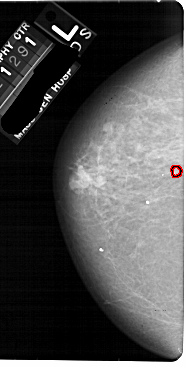

A_1868_1.RIGHT_MLO

RIGHT_MLO LINES 5491 PIXELS_PER_LINE 2866 BITS_PER_PIXEL 12 RESOLUTION 43.5 NON_OVERLAY

FILE: A_1868_1.LEFT_MLO.OVERLAY

TOTAL_ABNORMALITIES 1

ABNORMALITY 1

LESION_TYPE CALCIFICATION TYPE PLEOMORPHIC DISTRIBUTION CLUSTERED

ASSESSMENT 4

SUBTLETY 3

PATHOLOGY BENIGN

TOTAL_OUTLINES 1